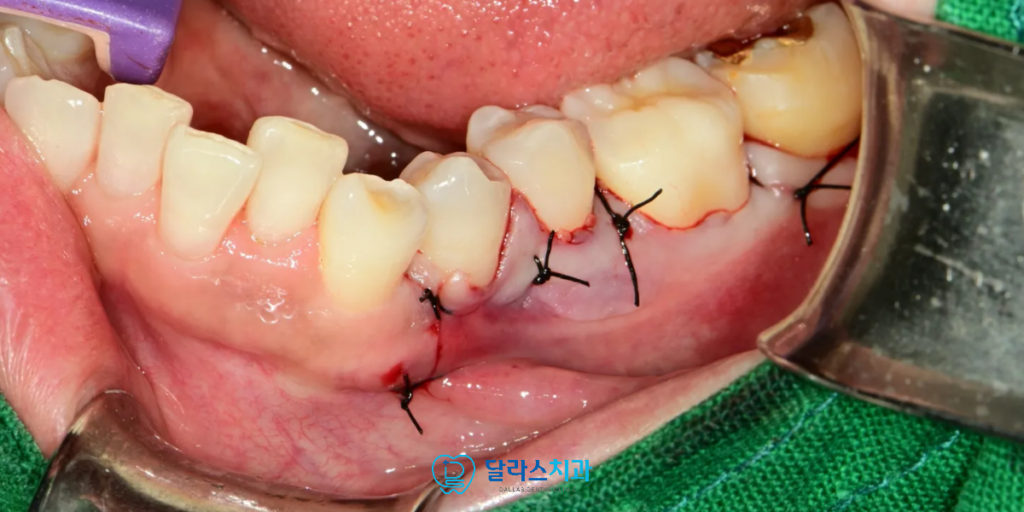

골융기 제거는 잇몸을 국소적으로 절개한 뒤

과도하게 자란 치조골 부분만을 다듬어 평탄하게 만들어주는 방식으로 진행합니다.

뼈를 완전히 제거하는 것이 아니라 돌출된 부분을 다듬는 형태이기 때문에

발치나 임플란트와 같은 큰 외과적 처치에 비해 부담이 훨씬 적고, 통증도 비교적 경미한 편입니다.

수술 과정에서 사용하는 기구들은 뼈를 정교하게 삭제하도록 설계되어 있어

주변 치아나 잇몸에 무리가 가지 않도록 세심하게 조절됩니다.